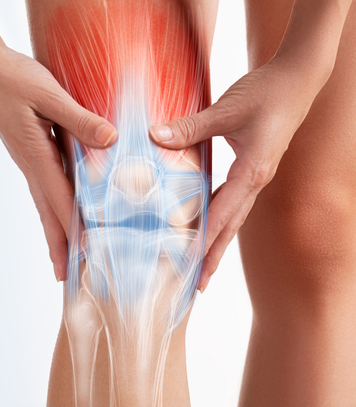

Knee Replacement

Advanced knee replacement surgery for pain relief and improved mobility.

Knee Replacement

Advanced knee replacement surgery for pain relief and improved mobility.